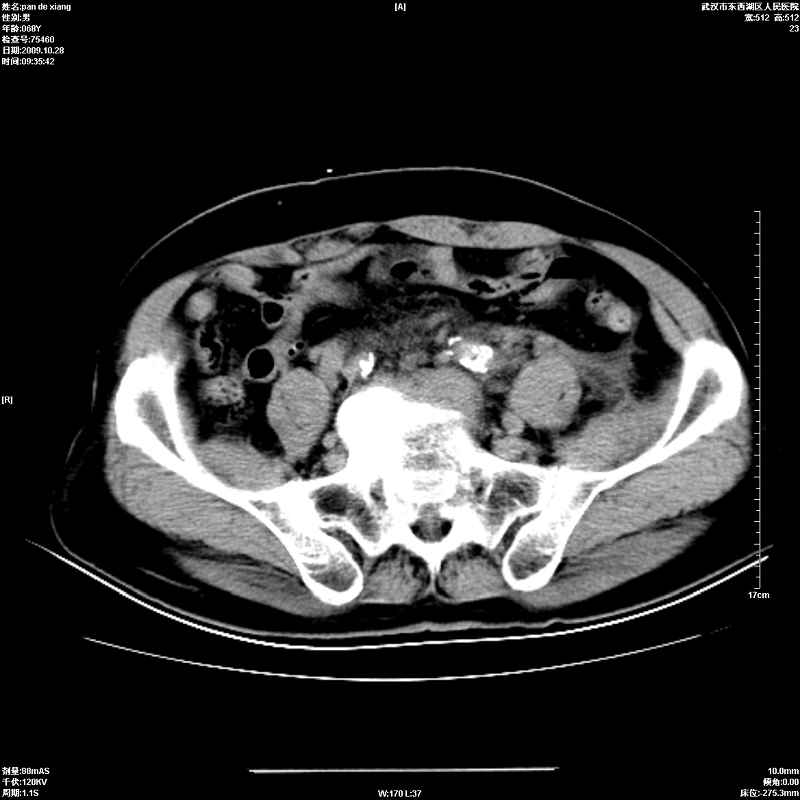

以下是引用杀毒软件在2009-10-28 20:41:00的发言:[br]结合临床考虑---白血病双肾改变或淋巴瘤。

以下是引用zxl51642在2009-10-29 9:59:00的发言:[br]结合临床“单克隆免疫球蛋白血症”,考虑双肾为继发损害并肾功能不全(尿中大量igg及少量iga、igm等大分子免疫球蛋白滤出所致继发损害),椎前软组织肿块为髓外造血。与浆细胞瘤有区别,平扫时有战友说的很清楚。